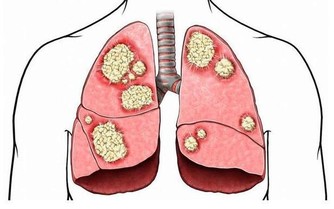

高血壓、膽結石、膽囊炎、乳腺增生、肝囊腫、肝血管瘤.…..都是肝氣鬱結所致,

這些肝經的鬱結熱毒,疏泄不出去,

輕則煩躁失眠,頭痛肋脹,

重則乳房容易長包塊,容易得子宮肌瘤,卵巢囊腫。

因為鬱結剛開始只是氣不得疏泄,久了無形的氣機,跟有形的痰血瘀血搏結在一起,就容易變成包塊。